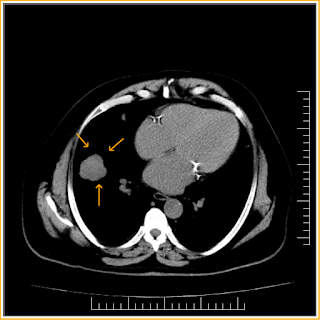

Incidentally detected lung nodule on CXR and followed up by CT, which shows lobulated outline lung nodule and mediastinal lymphnodes were also noted and biopsy was suggested for neoplastic etiology.

1. A lung nodule has been defined by the

Nomenclature Committee of the Fleischner Society as a rounded opacity, well or

poorly defined on a conventional radiograph, measuring up to 3 cm in diameter.

2. On computed tomography (CT) scan, a nodule

appears as a rounded or irregular opacity, well or poorly defined, measuring up

to 3 cm in diameter. Opacity less than 3

mm is defined as a micronodule.